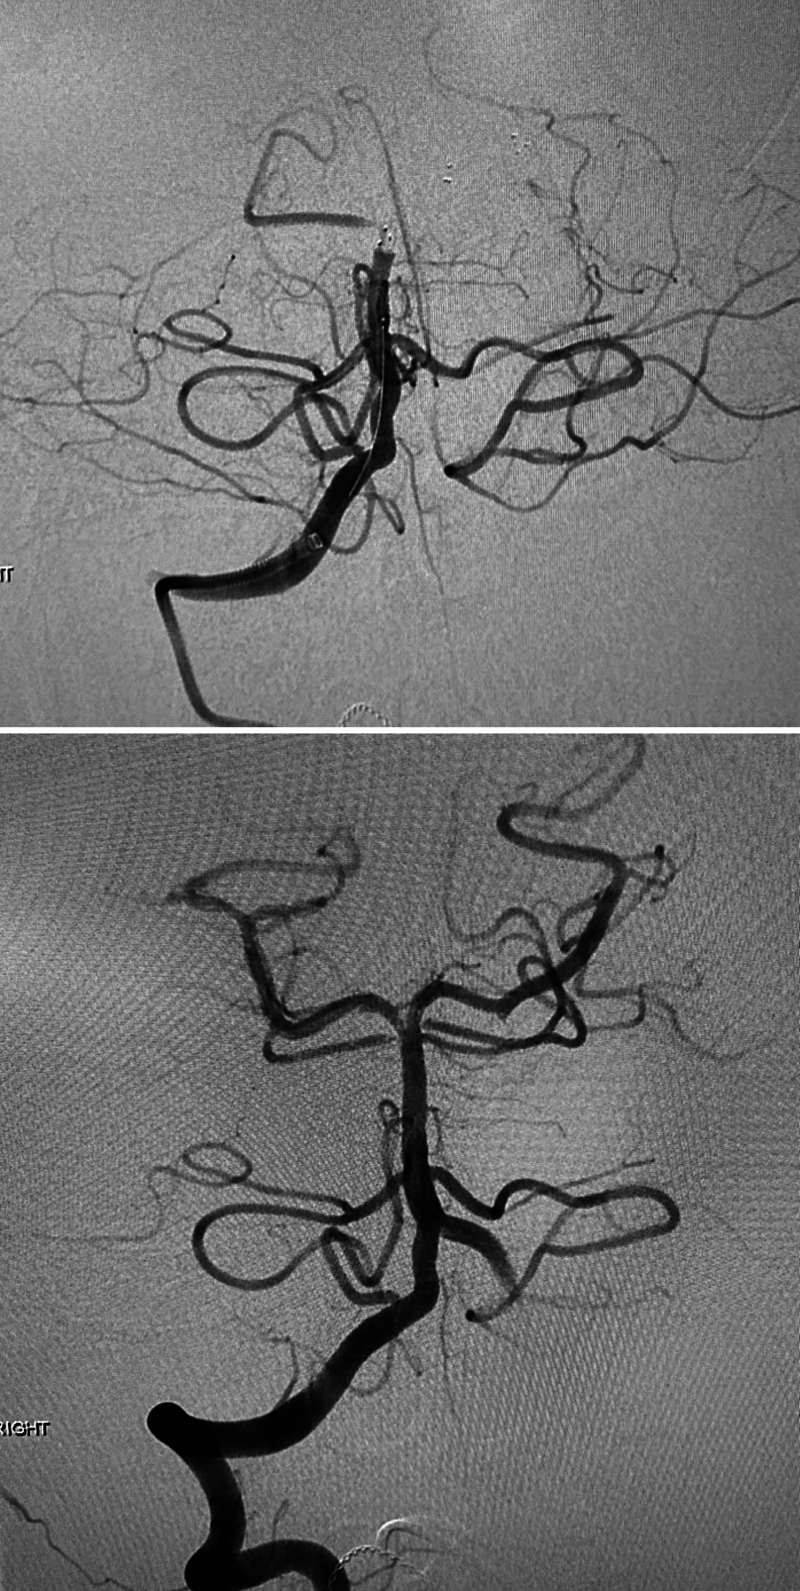

Observations: This case report discusses the management of a 13-year-old male with recurrent basilar artery occlusions and an associated vertebral artery dissection. Initially presenting with acute ischemic stroke symptoms, the patient underwent a successful thrombectomy with significant improvement in neurological function. He experienced a second stroke due to another basilar artery occlusion, which was subsequently treated by a thrombectomy. Further investigation revealed a vertebral artery dissection with a pseudoaneurysm, likely contributing to the stroke recurrence. Treatment adjustments included transitioning from aspirin to clopidogrel when aspirin resistance concern was noted, and finally apixaban therapy when the dissection was discovered. The patient remained stable without stroke recurrence.